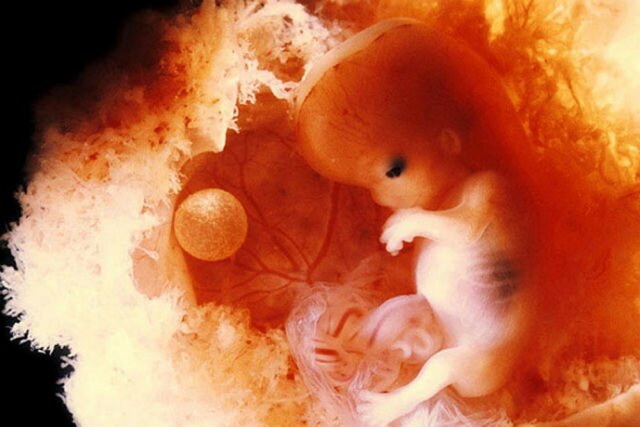

• Embrión

Durante la 12va semana se desarrolla en sistema nervioso, los esbozos de la columna vertebral y del cerebro.

Embrión

Comienza el desarrollo de las extremidades superiores e inferiores.

• Apreciación del feto

Apreciación del feto

Las extremidades y forma del feto se pueden apreciar de forma clara.